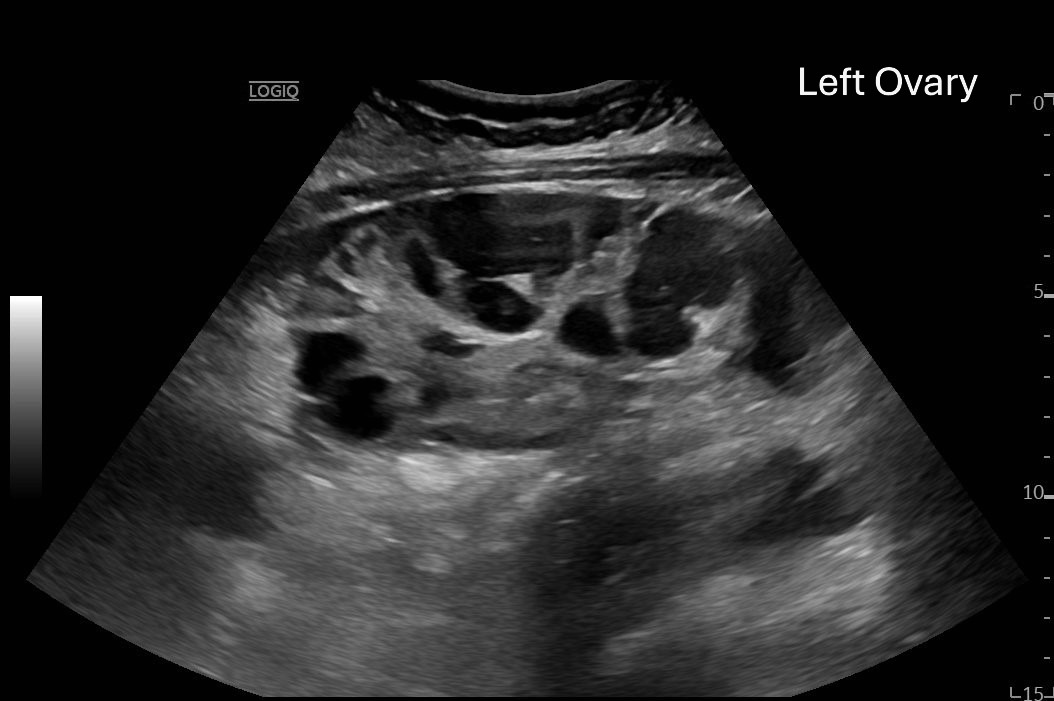

Ovarian hyperstimulation syndrome (OHSS) is a potentially life-threatening complication of assisted reproductive technology (ART). Here, we present the case report of a 30-year-old female undergoing infertility treatment who presented to the emergency department (ED) with nausea and vomiting, abdominal distention, and shortness of breath. On physical exam, she had notable ascites. Computed tomography (CT) of the abdomen and pelvis and pelvic ultrasound (US) revealed significant ascites and enlarged ovaries with multiple cysts. She was diagnosed with severe OHSS and admitted to obstetrics and gynecology (OBGYN) service for five days where she underwent intravenous (IV) hydration and paracentesis. This case report reviews the clinical presentation, categorization, management, and prevention of OHSS and provides examples of imaging findings consistent with the condition.